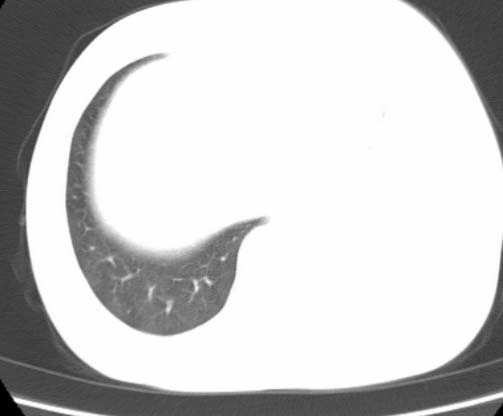

标题: CT25648:求教:是肺发育不全还是结核?

女  20岁。一月前咳血,诊“肺结核”抗痨治疗一月后,咳血停止,现复查。病人精神好。前后ct片对比未见明显变化。既往体检“正常”

1)考虑左肺结核并肺不张、支气管扩张。2)纵隔疝。

左肺发育不全。